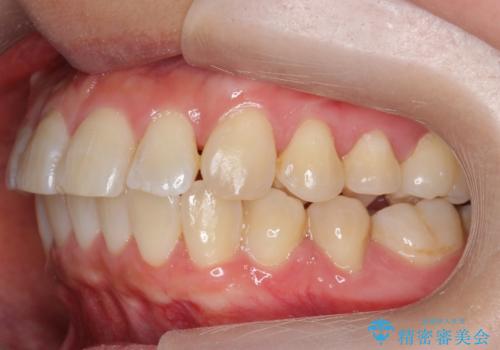

[ 前歯のねじれ・がたつき ] マウスピース矯正

![[ 前歯のねじれ・がたつき ] マウスピース矯正の症例 治療前](https://seimitsushinbi.jp/wp/wp-content/uploads/2024/02/4007c6479f6bce11863dcdd32ed5e39b-500x350.jpg?v=1708502552)

![[ 前歯のねじれ・がたつき ] マウスピース矯正の症例 治療後](https://seimitsushinbi.jp/wp/wp-content/uploads/2024/02/e7a01485e4f4dd0da04705fde4cc34cc-500x350.jpg?v=1708502585)